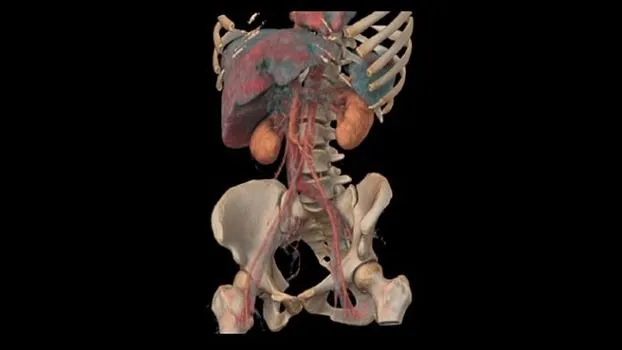

Клинические изображения

Клиническая эффективность

В КТ-исследованиях больше всего времени уходит не на само сканирование, а на подготовку пациента, реконструкцию изображений и создание заключительного отчета. С Revolution Ascend вы можете легко размещать пациентов с высоким ИМТ на столе и эффективно проводить интервенционные процедуры и любые другие исследования нажатием всего лишь двух кнопок.